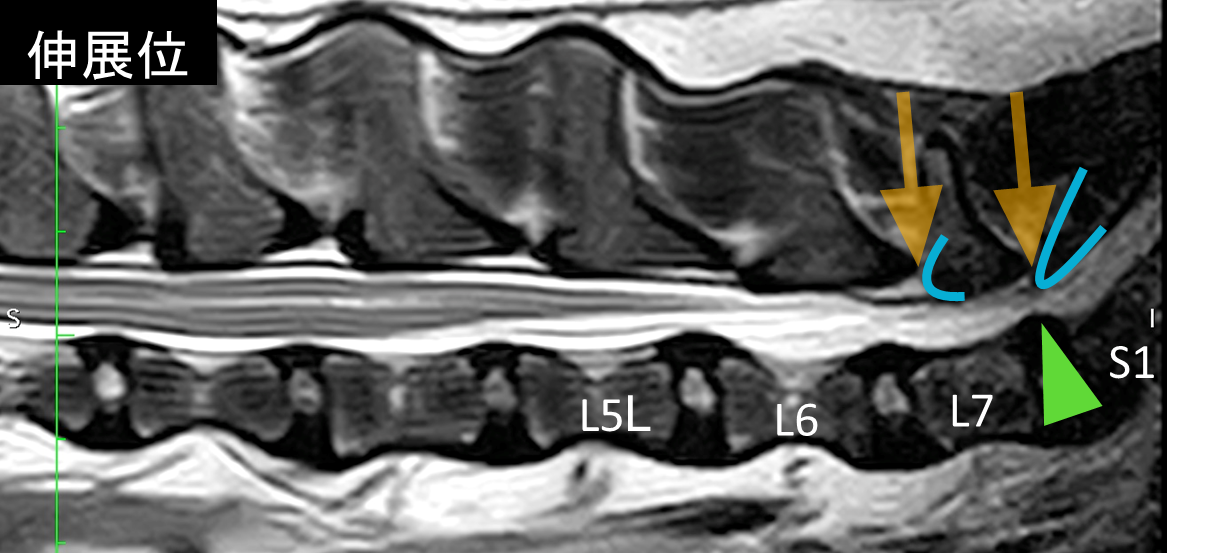

診断にはMRI検査や脊髄造影検査が必要となります。下の画像はこの病気のMRIになりますが、画像を撮影しているときは動かすことができないので、腰を伸ばした状態(伸展位)と曲げた状態(屈曲位)で分けて撮影しています。

この症例では、伸展位で馬尾領域が背側と腹側から圧迫されている所見が認められます(青いラインの背骨が前の背骨と重なってオレンジの隙間が短いことがわかります。緑色の椎間板も馬尾神経を圧迫しています)。伸展位で認められた圧迫所見は屈曲位では解消されていることがわかります。